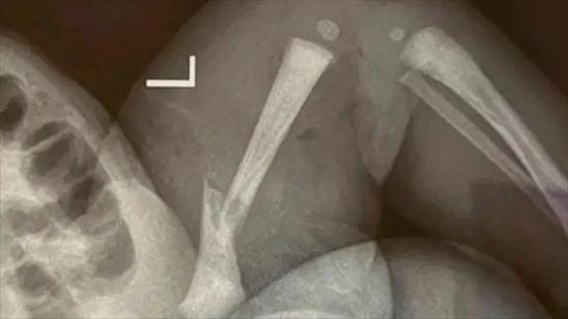

·江蘇靖江新生兒骨折家長質(zhì)疑系醫(yī)療事故,靖江市人民醫(yī)院:手法不熟導致。